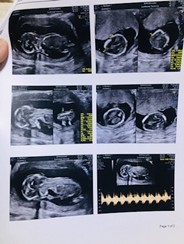

รูปซาวด์เด็กน้อย 3 เดือน

12w+4 ยังไม่เห็นเพศเลยค่ะ ใครดูออกมองให้เค้าหน่อย หมอ ไม่ยอมบอก ขอดูรูปซาวด์เด็กๆ3เดือนหน่อยค่ะ อยากเห็นๆ #ขอบคุณล่วงหน้านะคะ

13วีค3วัน หมอยังไม่ดูเพศให้เลยคะ

12w5dยังไม่เหนเพศเหมือนกันจ้า